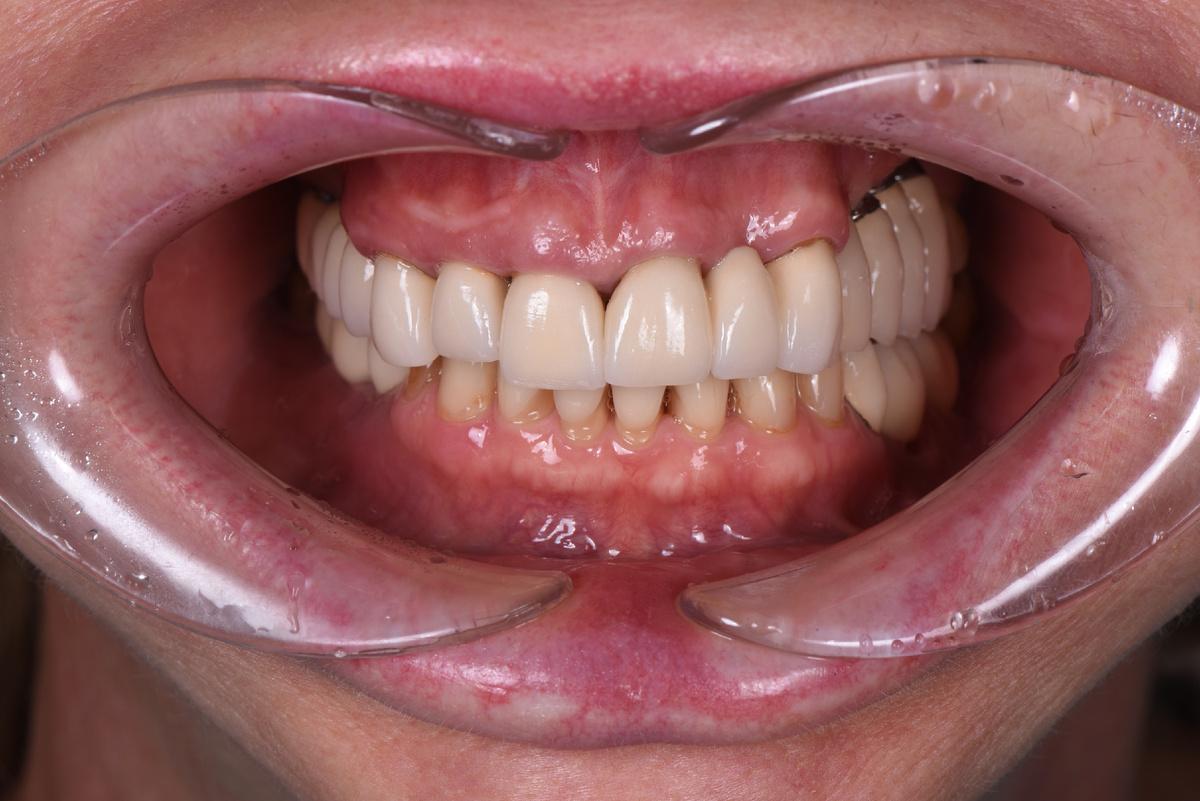

Как выглядит результат спустя несколько лет — на пяти фотографиях ниже

Верхний зубной ряд:

-

Справа. Протяженный мост на 5 единиц с опорой на 3 свои зуба

Передние зубы. Две одиночные коронки + мост на 3 единицы

Слева. 4 коронки с опорой на 4 импланта + зуб мудрости

Нижний зубной ряд:

Справа. Мост на 3 единицы с опорой на 2 импланта + дистопированный зуб мудрости

Передние зубы. 8 собственных +/- живых зубов

Слева. 1 свой зуб под коронкой, 2 коронки с опорой на 2 импланта + дистопированный зуб мудрости